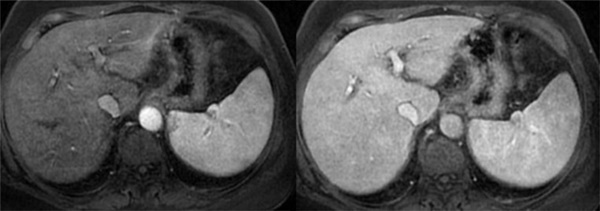

Hình ảnh về tác dụng của phương pháp cộng hưởng từ đặc hiệu mô gan.